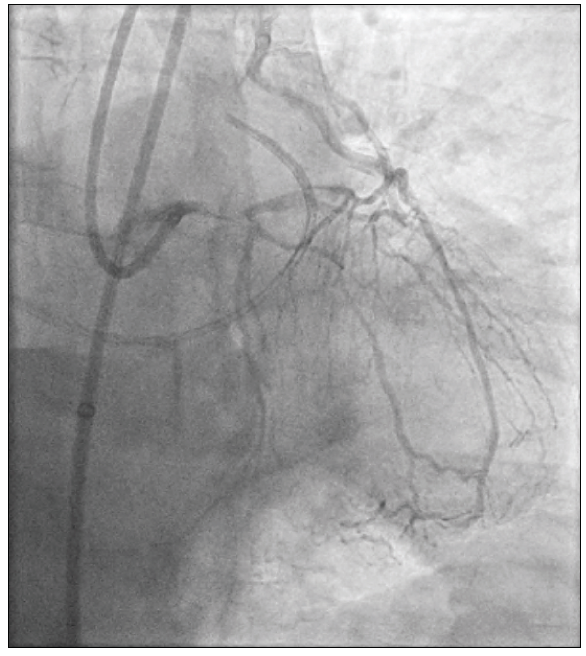

The patient began to complain of his usual back and leg pain shortly after sheath delivery. Although angiography demonstrated no injury to the aorta or its branches from placement of the sheath, it did confirm near occlusion of the infrarenal aortic lumen by the sheath. After careful consideration, the procedure was continued with a 7-F extra backup 3.5 guiding catheter to intubate the left coronary ostium. Dual-injection angiography of the LMCA and LIMA grafts was performed to define the features of the LMCA CTO (Figure 2). A recanalization attempt was undertaken; however, shortly after delivery of a retrograde microcatheter into the proximal LAD artery via the LIMA graft, the patient became profoundly hypotensive with marked ST-segment depressions. Despite supportive measures, the procedure was terminated due to the patient’s hemodynamic instability (secondary to microcatheter obstruction across a proximal LAD artery lesion). A reattempt of percutaneous coronary intervention (PCI) to the LMCA occlusion was planned using hemodynamic support with an Impella CP device (Abiomed, Inc.).

Figure 3. The Impella single-access technique (A). After placement of the 14-F Impella CP sheath, a micropuncture needle was used to puncture the hemostatic membrane near one of the four corners of its hub. The micropuncture sheath was then placed through the puncture point, through which a supportive wire was advanced into the aorta. The micropuncture sheath was then removed, and the puncture was sequentially dilated to allow placement of a 7-F Destination sheath. The final result of the CTO PCI of the LMCA (B).

Using a retrograde approach, the LMCA CTO was crossed using a hydrophilic wire. This was exchanged for an externalization wire, over which PCI from the LMCA into the LAD artery was performed. An excellent final result was achieved (Figure 3B), and the Impella catheter and 7-F Destination sheath were explanted. A supportive wire was left across the aortic lesion through the Impella sheath, along which a long 7-F sheath was reintroduced.